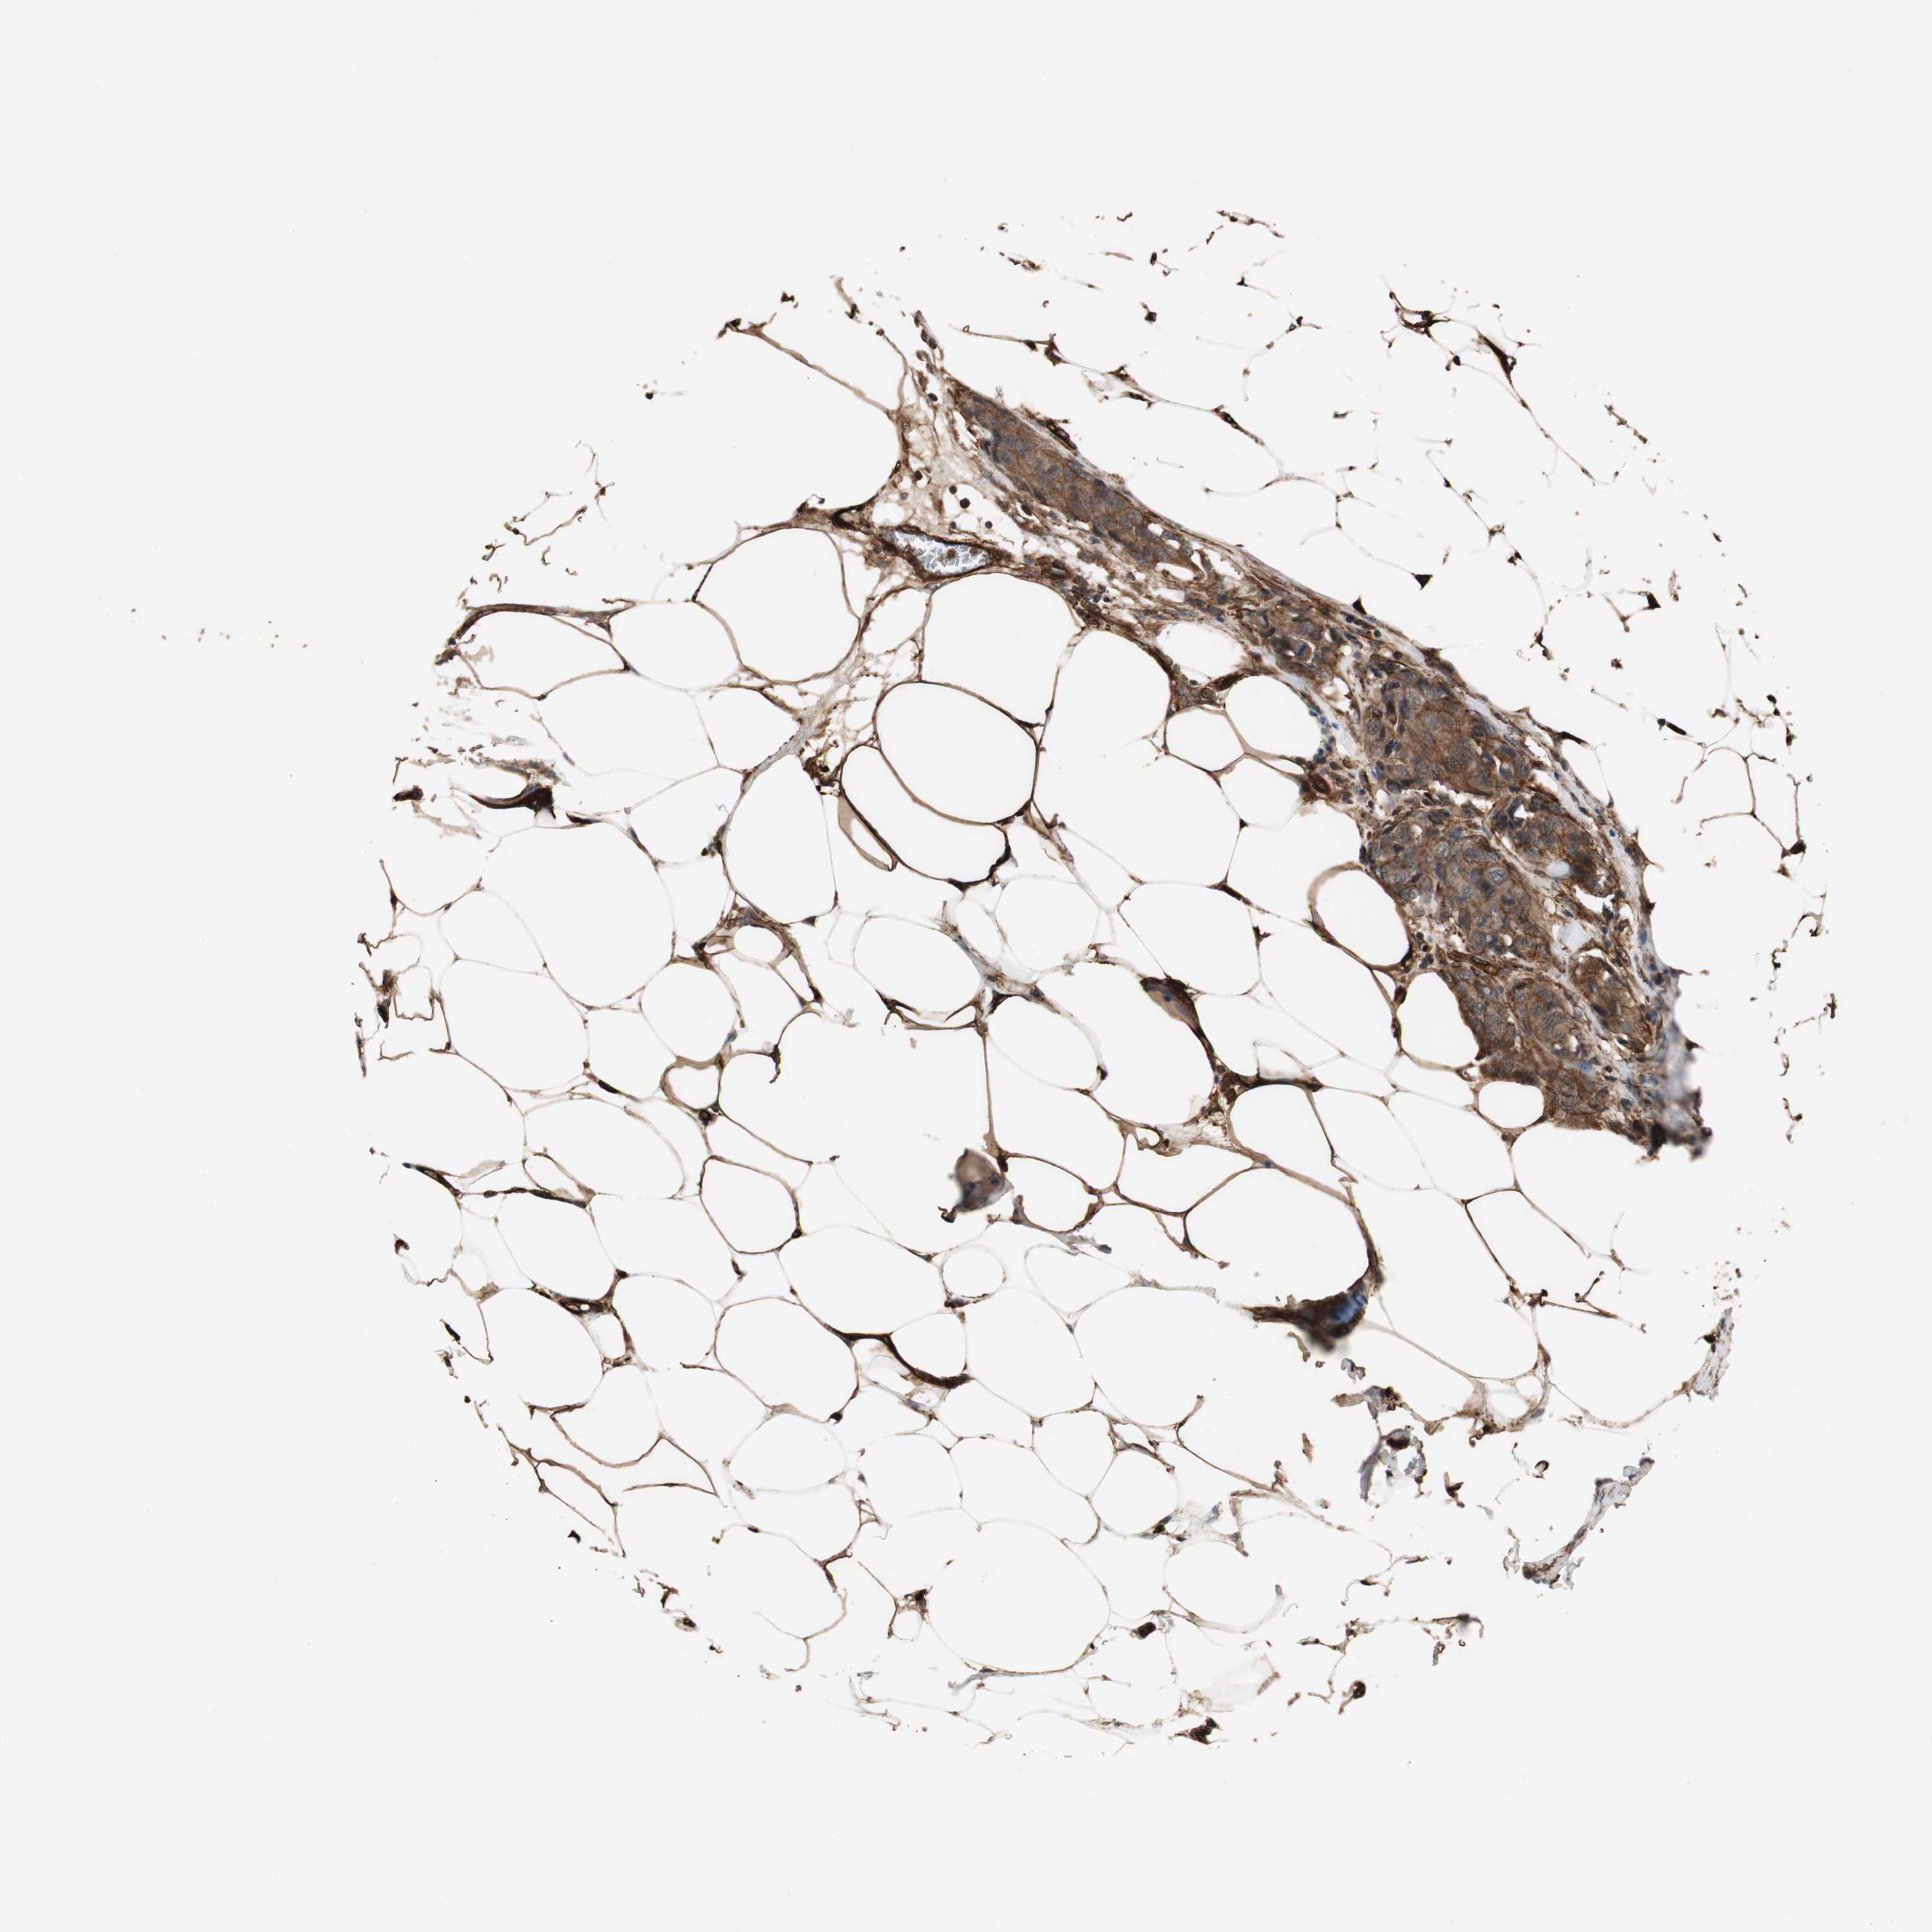

BRCA TCGA BRCA VALIDATION PROTEIN EXPRESSION

ANTIBODIES

AND

VALIDATION